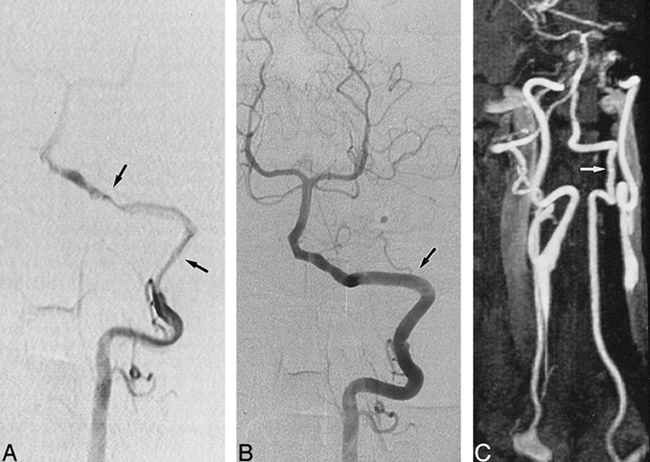

A 37-year-old man with neck pains and vertigo after minor cervical trauma.

A, T1-weighted axial MR image (obtained 1 day after B) at the C3−C4 level, shows a typical aspect of dissection of the right VA, including a crescentic high signal (arrow) of the mural hematoma surrounding a narrowed signal void (arrowhead) of the residual lumen.

B, Arch aortogram with oblique view. The left VA appears normal (arrow), whereas the right VA is not visible, suggesting its complete occlusion. A selective angiogram of the right subclavian artery confirmed the diagnosis of VA occlusion.

C, Oblique view selective angiogram of the right VA, obtained at 3 months, shows recanalization of the artery (arrow) without residual luminal irregularities.

D, Contrast-enhanced MR angiogram, obtained at 8 months, with selective subvolume MIP reconstruction of VAs, shows a normal appearance of the right VA (arrow), consistent with findings revealed by conventional angiography.